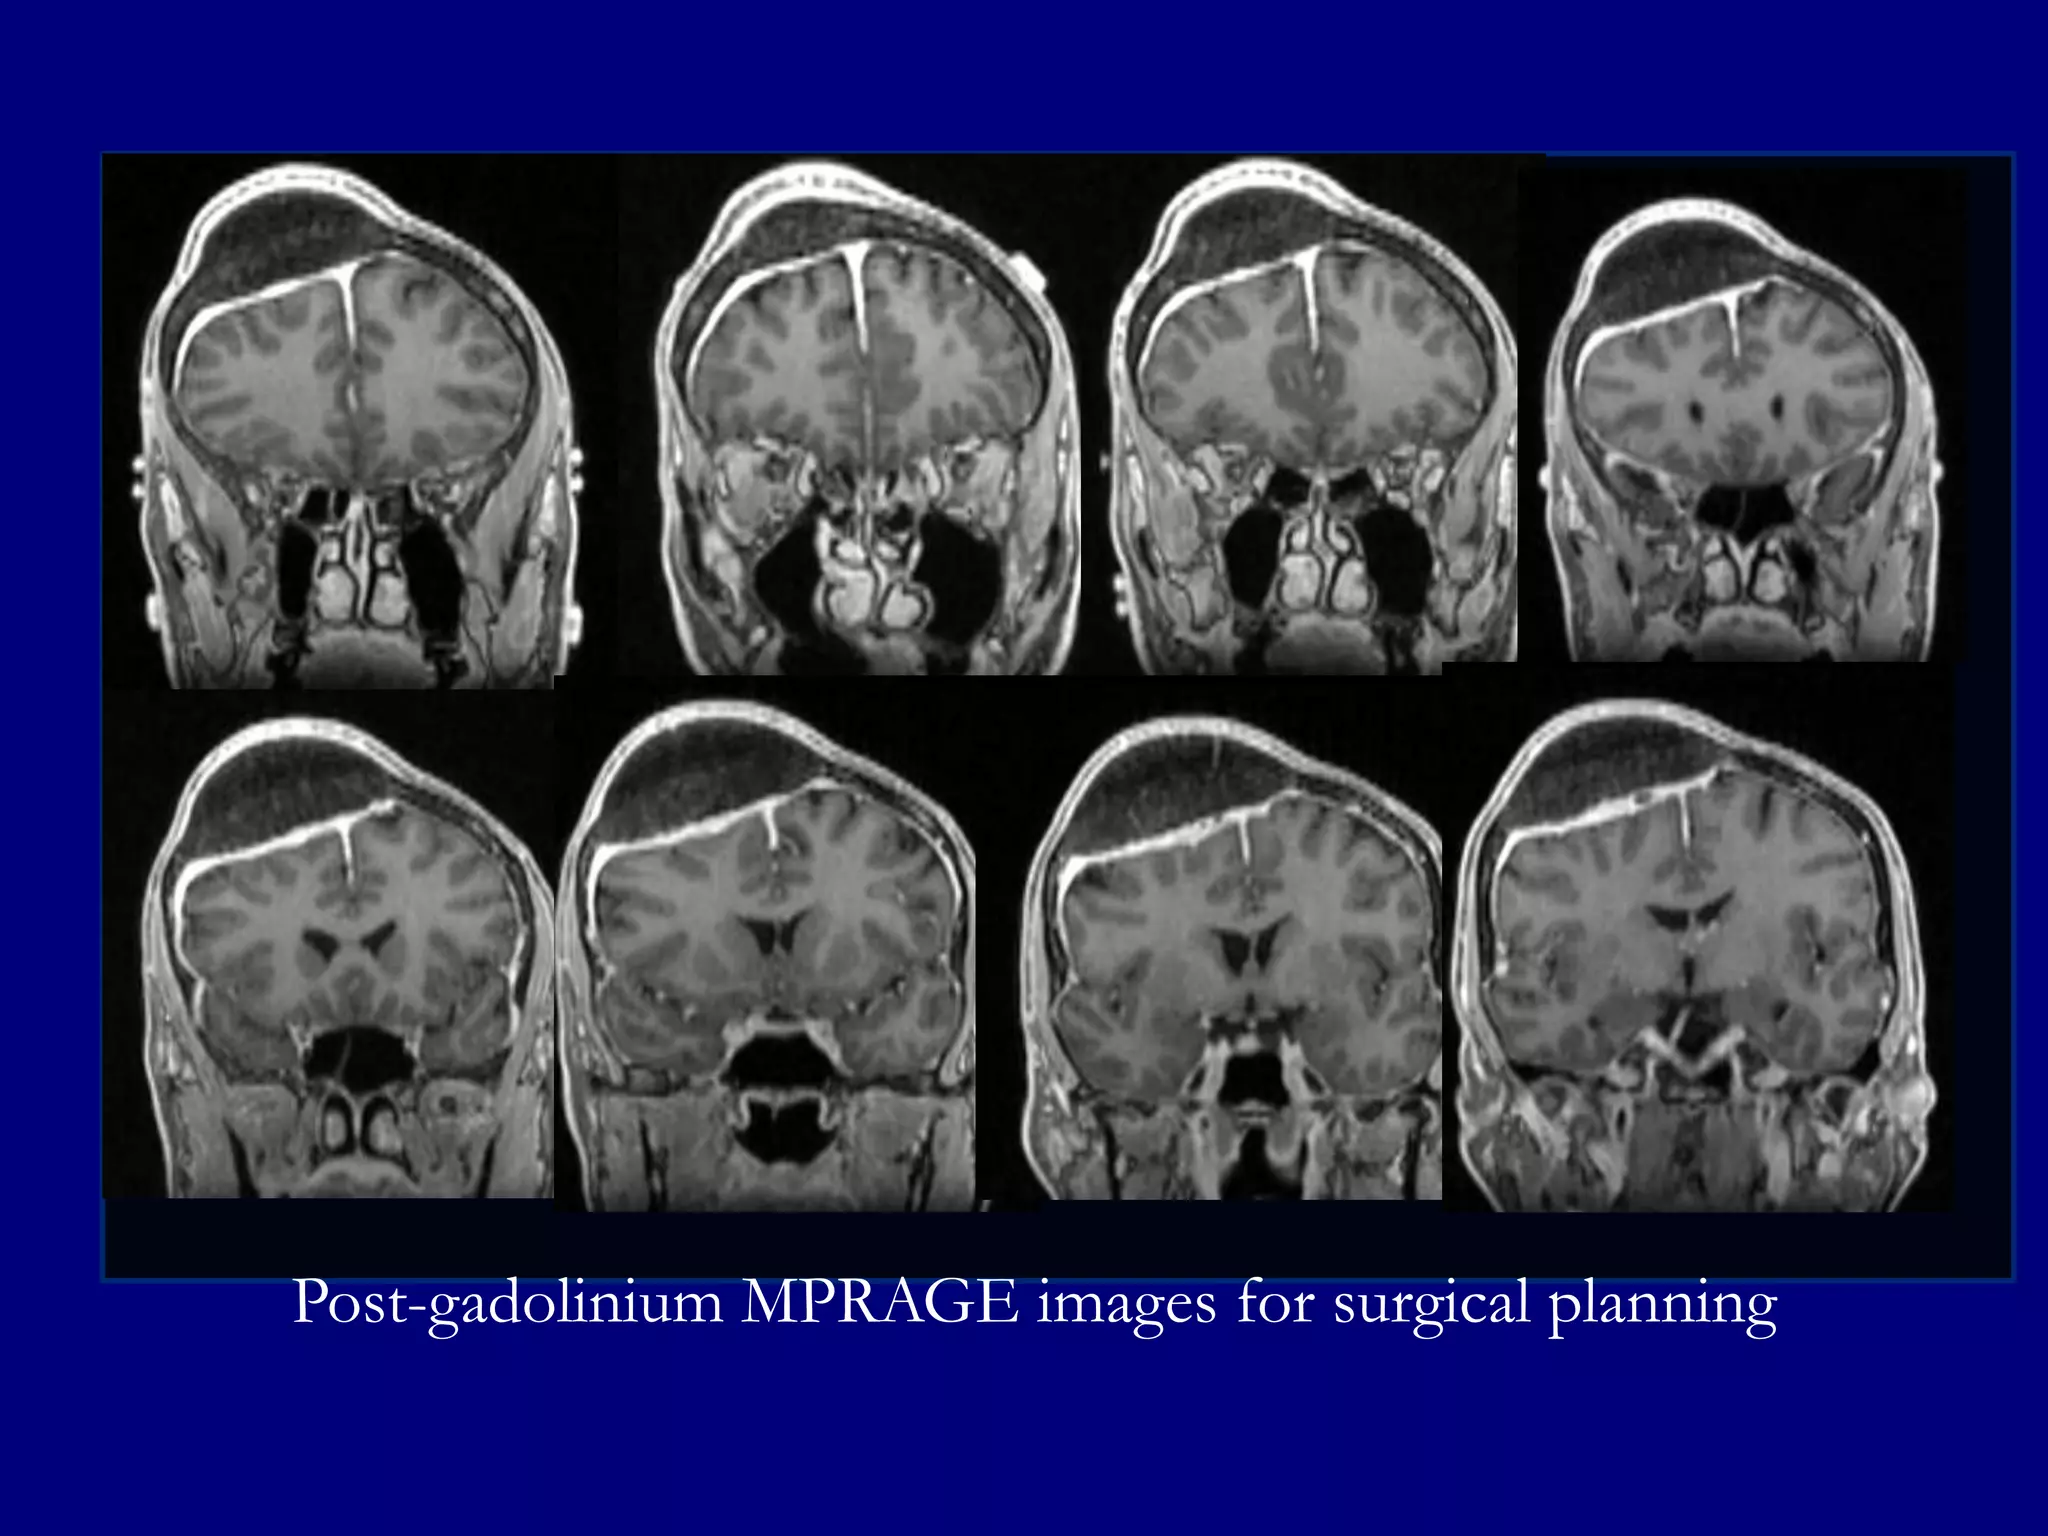

Magnetic Resonance Imaging

Post-gadolinium MPRAGE Sagittal and Coronal

Post-gadolinium MPRAGE Axial for Surgical Planning

MRI

Low signal central portion on T1 and T2-weighted

images indicating fibrosis

 Enhancement at the margins suggestive of

hemangiomatous active component of the disease